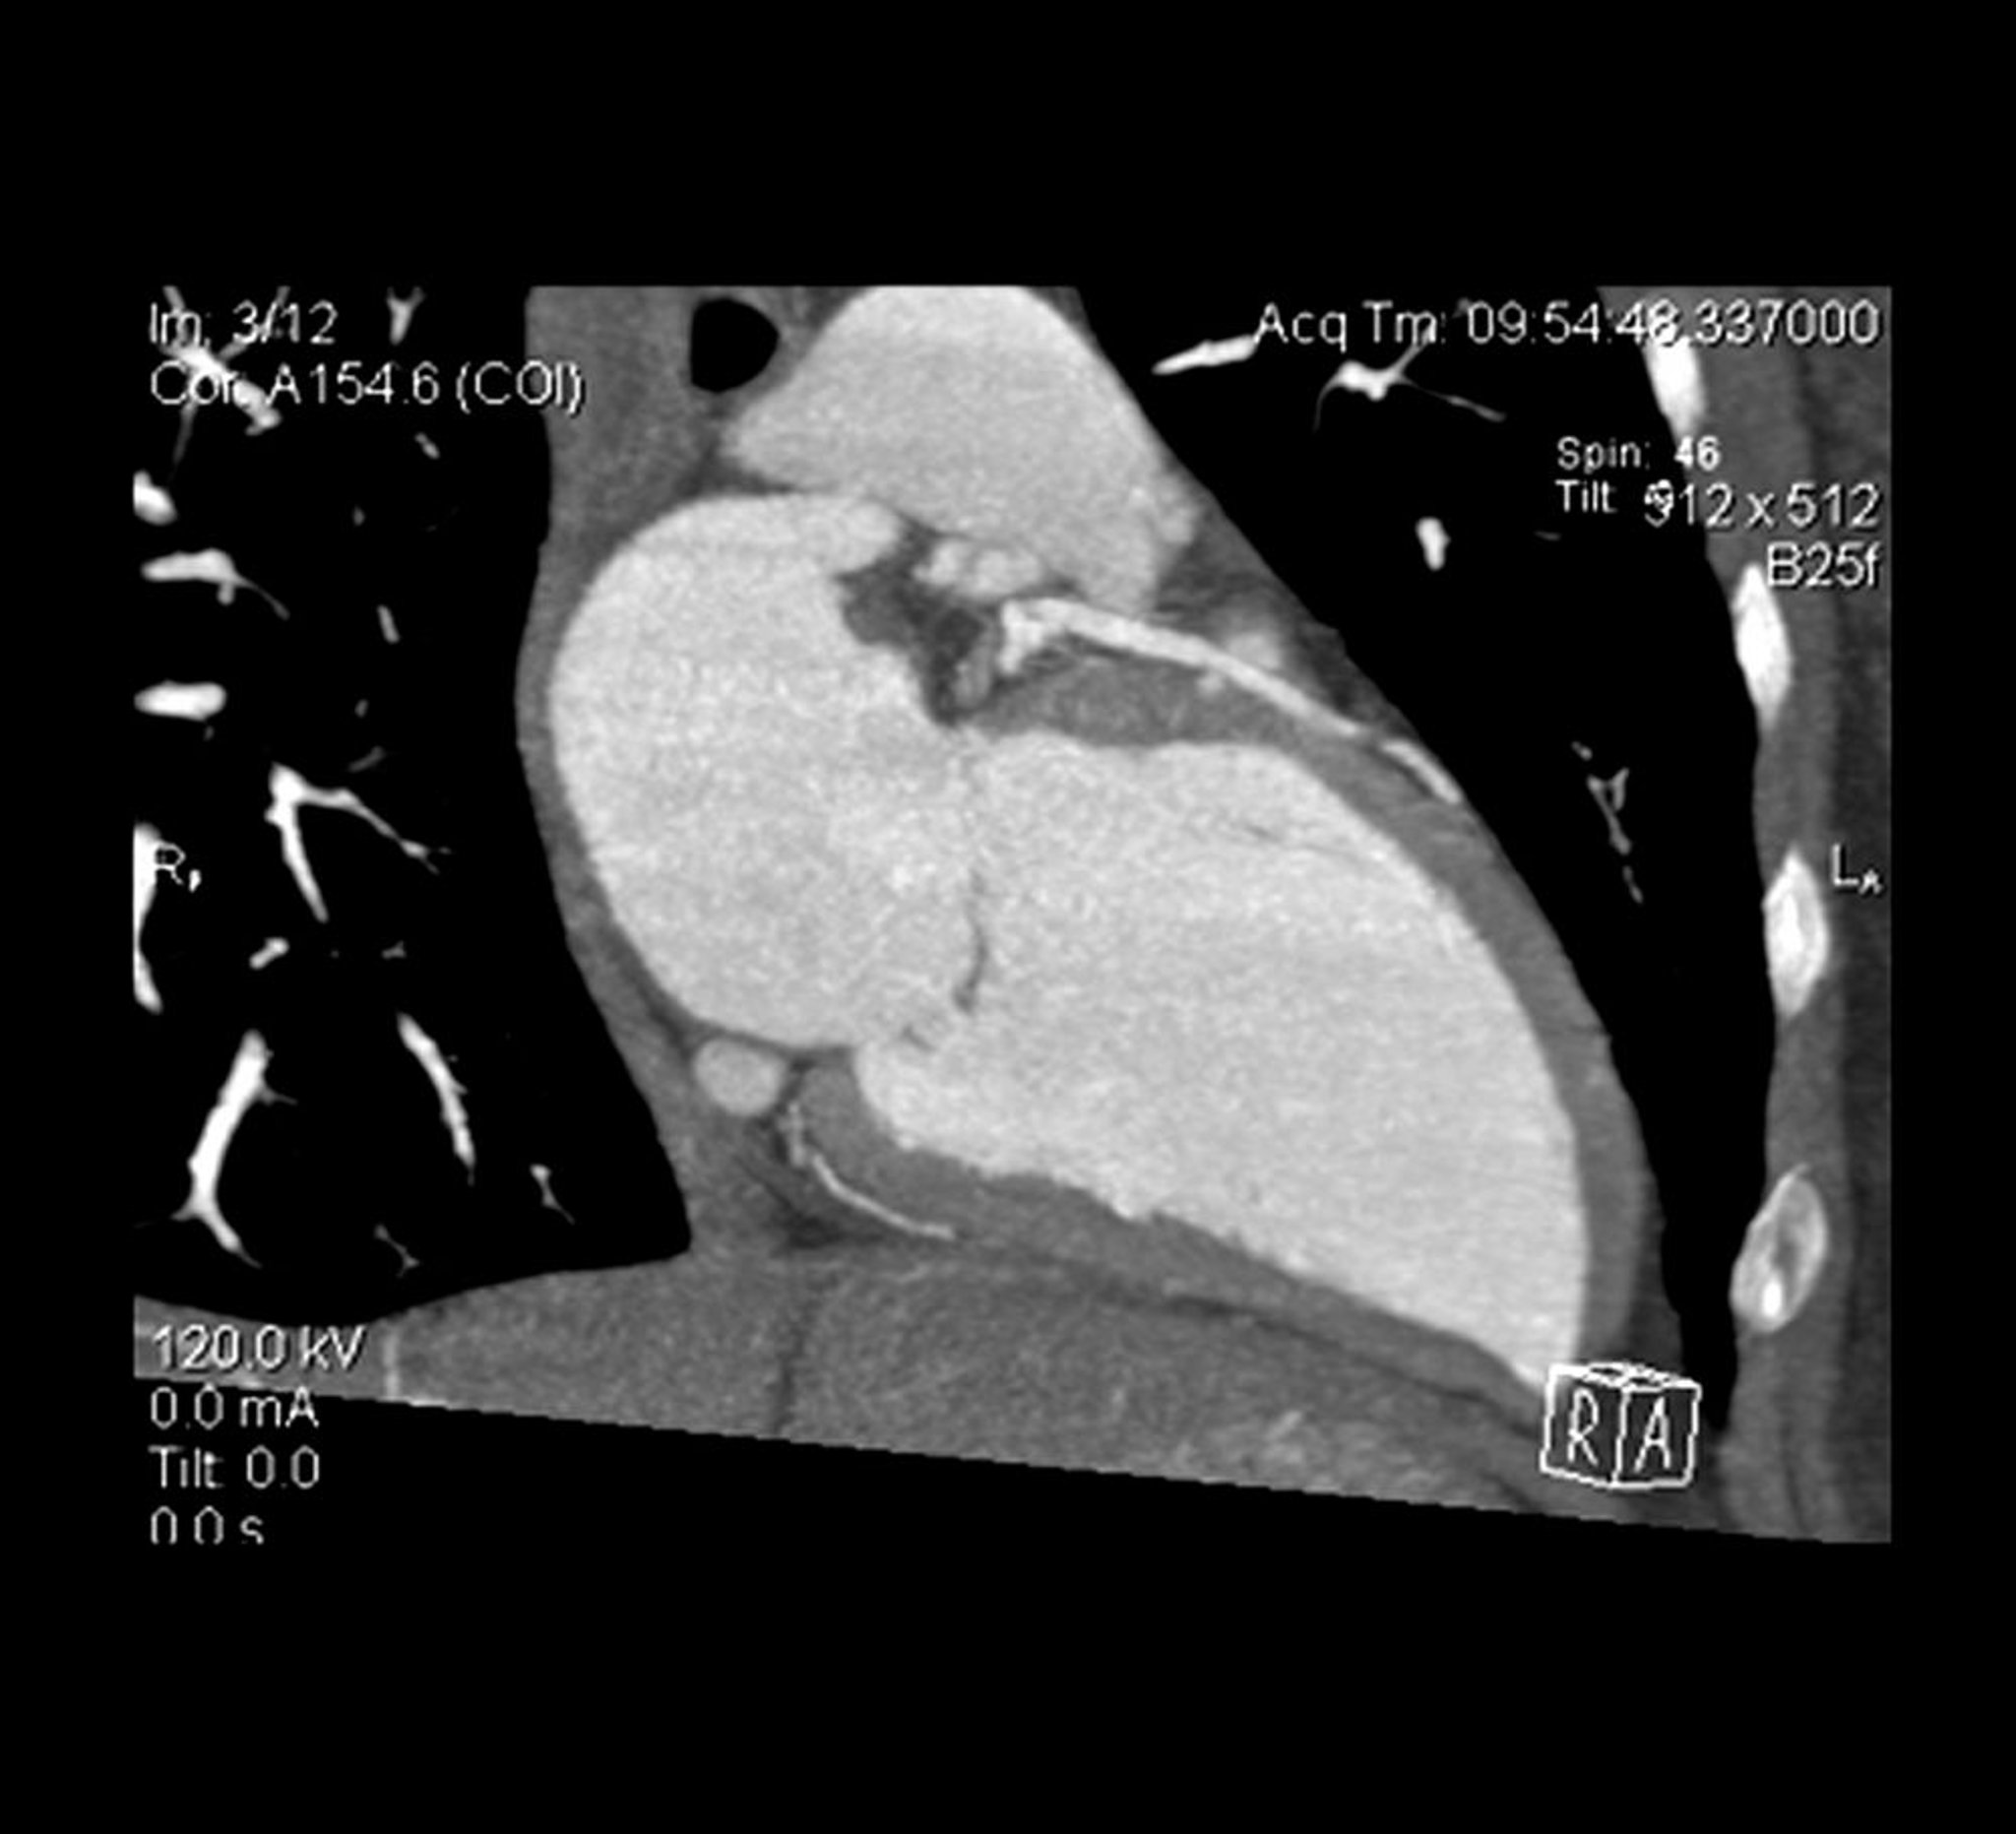

La sezione trasversale di un angio-TC cardiaca mostra il ventricolo sinistro e l'arteria discendente anteriore sinistra.